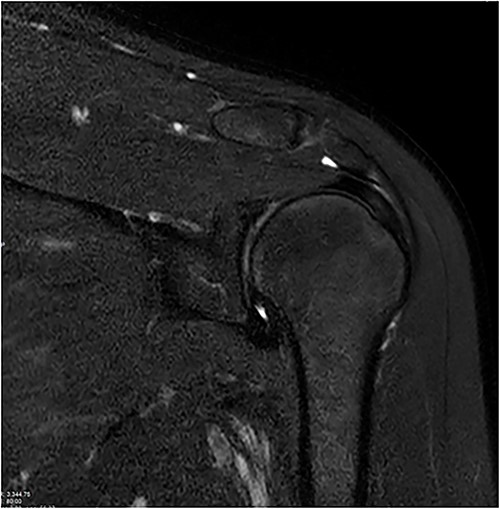

Standard anterior/posterior and lateral X-rays of the affected shoulder were done. The patient was diagnosed with adhesive capsulitis. She was therefore referred to office-based extensive rehabilitation program to improve range of motion and strengthen shoulder muscles. Though MRI does not play a rule in the diagnosis and management, we opted to do one, after consenting the patient, trying to understand the peculiarity of the case (Figs 1 and 2).

Coronal and axial T2 fat saturated image of left shoulder showing thickened inferior capsule of low T2 signal, characteristic of freezing phase in adhesive capsulitis.